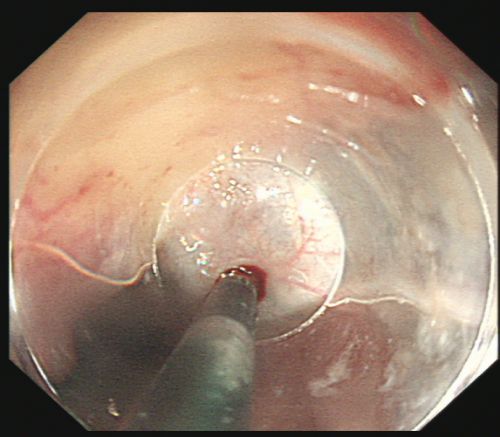

省医岳麓山院区综合内科彭娅主任团队为患者施行胃镜下食管曲张静脉套扎及硬化剂注射治疗。

治疗后,创面无活动性出血。

由于血管压力高,手术风险大,术中发生大出血、窒息及异位栓塞的风险非常高。综合内科主任彭娅反复与家属沟通取得理解配合后,为易某实施改良后内镜下止血技术——食管曲张静脉套扎+硬化剂注射治疗。所幸手术过程顺利,术后继续予以降门脉压力、护胃、减轻腹水、维持内环境稳定等对症支持治疗。经过积极治疗,患者病情趋于稳定,已恢复饮食,精神状况好转,于215日出院。